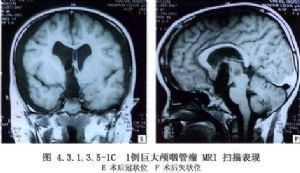

2.极少数始发于鞍上池的颅咽管瘤突破第三脑室底部或终板,进入第三脑室,且有时进入侧脑室,形成一个很大的脑室内瘤块。多见于较大儿童或成人,且实质性瘤块较囊性者更多,这种肿瘤虽可经额下入路手术,但对于其脑室内瘤块巨大者则需采用经脑室入路。

2.肿瘤显露 经胼胝体或经额叶皮质进入侧脑室后,沿脉络丛和丘纹静脉向前达室间孔,可见第三脑室内紫褐色肿物,有时该瘤通过室间孔突入侧脑室,可为囊性,或有钙化的实质性瘤块。

3.肿瘤切除 经室间孔显露肿瘤后,注意分辨其后下方的丘纹静脉由此穿入室间孔,与大脑内静脉相连,其上被覆侧脑室脉络丛(图4.3.1.3.4-2,4.3.1.3.4-3)。如肿瘤较小,室间孔未扩大,可于其前方切开一侧穹隆柱;如肿瘤较大,也可采用经脉络膜裂入路。肿瘤较软可被吸引器推动者,可于穿刺吸除囊液后,囊壁塌陷,再将其分块切除。CUSA是最理想的肿瘤切除工具,它不需要较大的暴露空间,还可用CO2激光切除囊内实质性瘤块,直至瘤壁变薄与脑室壁分开时为止。瘤壁向内推移,分离其与第三脑室的界面,用小棉片铺垫在肿瘤与脑室壁之间,使肿瘤向中央移动而脑室壁不为手术器械所伤。这样对于小的囊性颅咽管瘤且与脑室壁粘连不多者,可达到完全切除。

巨型第三脑室内颅咽管瘤常侵及脑室外结构,如视神经、视交叉、颈内动脉等,肿瘤基底常与周围结构粘连固定。从脑室内切除肿瘤时,需结合术前CT、MRI等影像检查资料与术中所见进行操作,要特别注意Willis动脉环前部发出的肿瘤供应血管,有时还有基底动脉系统发出的分支。肿瘤本身无血管,切除时出血不多,但与上述血管很难分离。如肿瘤较大且为实质性,周围粘连较紧,甚难完全切除,可行囊内及囊壁部分切除,打通室间孔,使脑积水好转,或者于瘤腔内置Ommaya贮液囊,以便日后肿瘤复发时经其穿刺抽吸囊液,亦可经其注入药物或核素。肿瘤切除后要注意脑脊液流通的情况,如室间孔开放不满意可切开透明隔,或行脑室-小脑延髓池或脑室-腹腔分流术,以解除梗阻性脑积水。